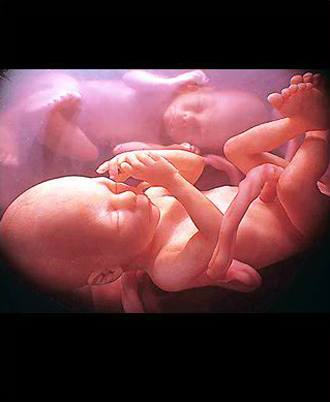

- 임신 증상진단

- 뚜렷한 임신증상이 없을 수 있습니다.

증상:입덧, 피로, 빈뇨, 두통 등 - 임신확인 검사

배란일로 보터 일주일 이후가 되면 임신테스트기로 임신사실이 확인됩니다.